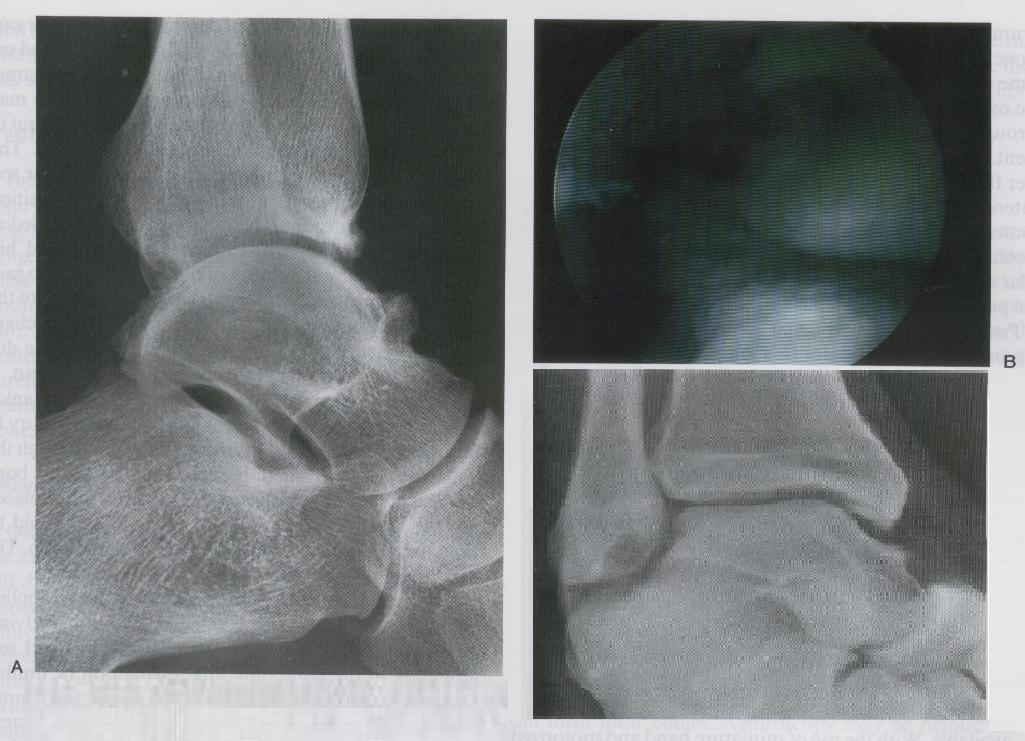

ARTROSCOPIA DEL TOBILLO POR ENFERMEDAD ARTICULAR DEGENERATIVA

RAZURADO DE HUESO ATRAGALINO (PICO DE GALLO)